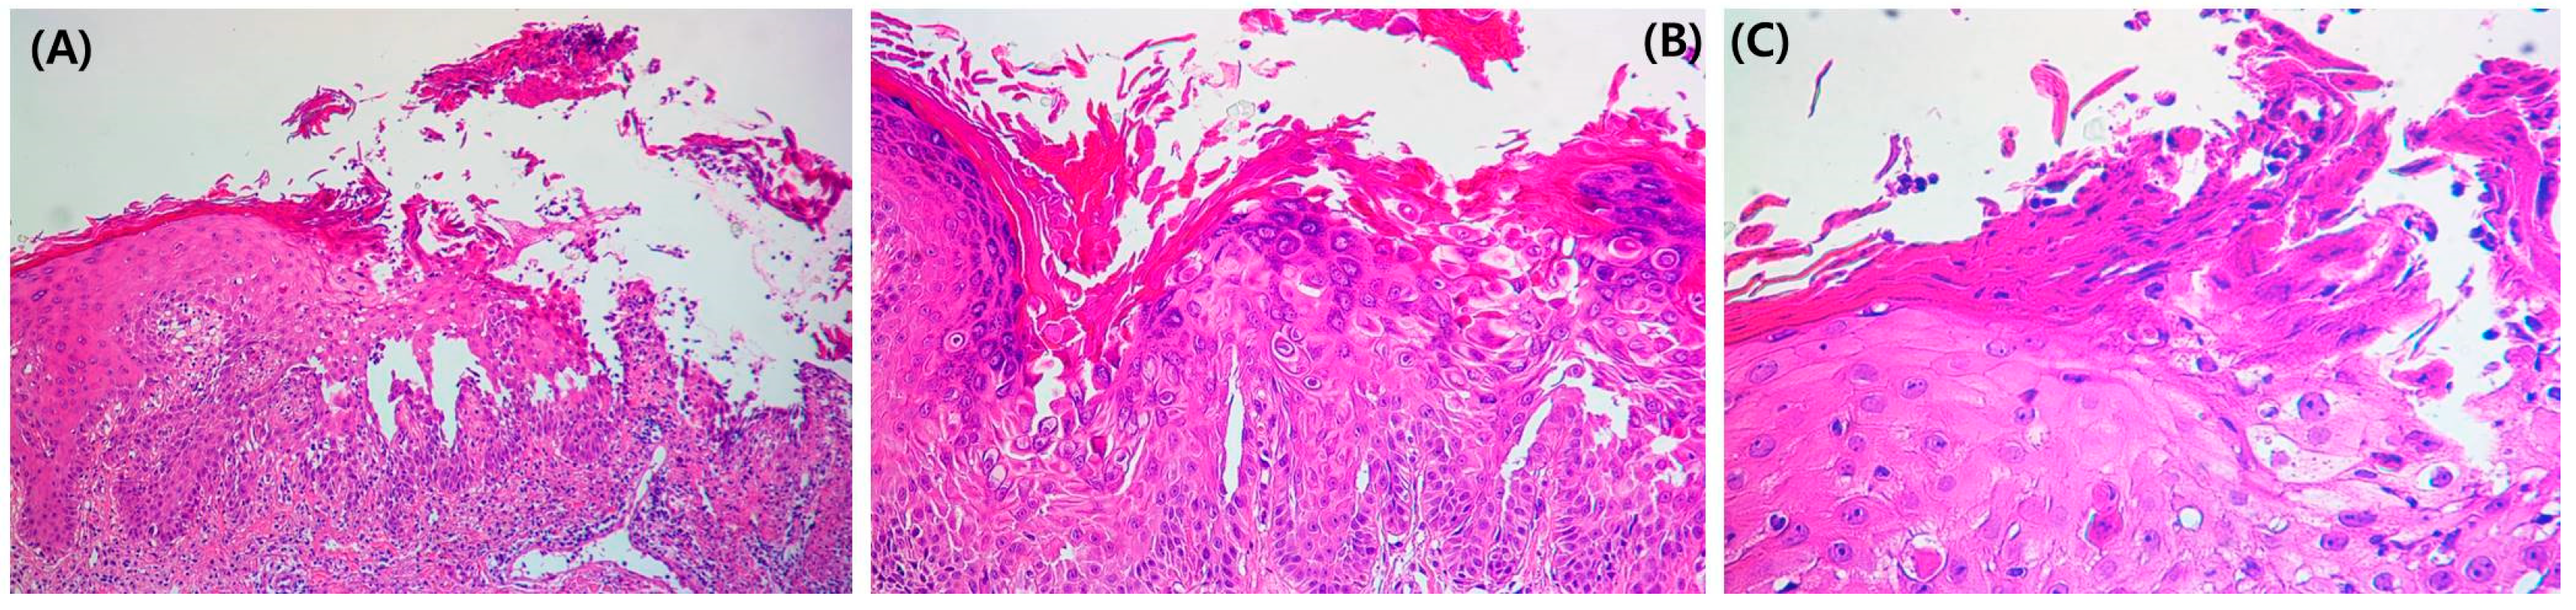

The treatment was changed to guselkumab, after which he improved for 4 months; however, the condition of the skin lesions waxed and waned repeatedly. A punch biopsy was performed on the abdominal lesion. Focal acantholysis was present in the suprabasal layer of the epidermal erosion area (Figure 3A). Dyskeratosis and corps ronds, pyknotic nuclei, and a clear perinuclear halo (Figure 3B) were observed in the epidermis. Corps grain compressed cells with elongated nuclei were seen in the stratum corneum and granular layer (Figure 3C).

Figure 3. (A) Focal acantholysis was present in the suprabasal layer of the erosion area in the epidermis (H&E 100×). (B) Dyskeratosis and corps ronds, pyknotic nuclei, and a clear perinuclear halo (H&E 200×) were observed in the epidermis. (C) Corps grain compressed cells.